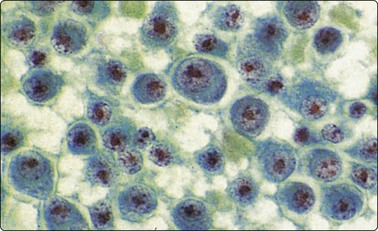

image image

Fig. 5.37 Follicular (grade 1) lymphoma

(A) Predominance of medium-sized cells with irregular, sometimes cleaved nuclei; a few centroblasts with multiple nucleoli. Relatively few small lymphocytes; (MGG, HP). (B,C) Kappa/lambda staining in cytospin preparation showing lambda monoclonality (B) (immunostain, alkaline phosphatase method, IP).

Criteria for diagnosis

1 lymphoid population composed of a mixture of centrocytes and centroblasts,

2 centroblasts with large round or slightly irregular nuclei, small nucleoli and basophilic cytoplasm,

3 centrocytes, small to medium-sized, with irregular or cleaved nuclei, inconspicuous nucleoli and little cytoplasm with a tendency to form clusters,

4 usually a relatively low number of small lymphocytes (Fig. 5.37A),

5 immunophenotype: monotypic SIg (Fig. 5.37B,C), CD19, CD20, CD10 (in 60–90% of cases), Bcl-2, Bcl-6, CD23 sometimes,

6 aberrant immunophenotype: CD5 (floral variant),

7 genetics: t(14;18) in over 90%.